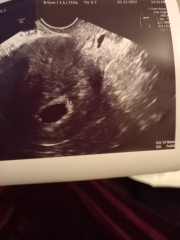

She checked me with speculum, all looked closed and good, almost no discharge at that time, but she said it's earlier than 6 weeks (!!!) , looks like 5w 4d and there was no baby and, just 17mm pregnancy follicle.😥

She didn't seem to be worried.

She said it's so early and she has seen hundreds of pregnancies like this and that it'll all show up in 2 weeks...

I kept on asking if it's blighted ovum (which was in my nightmares from the beginning), but she claimed it would have been bigger (it grows faster than a proper pregnancy follicle).

I was expecting to be 6w today and hear a heartbeat.